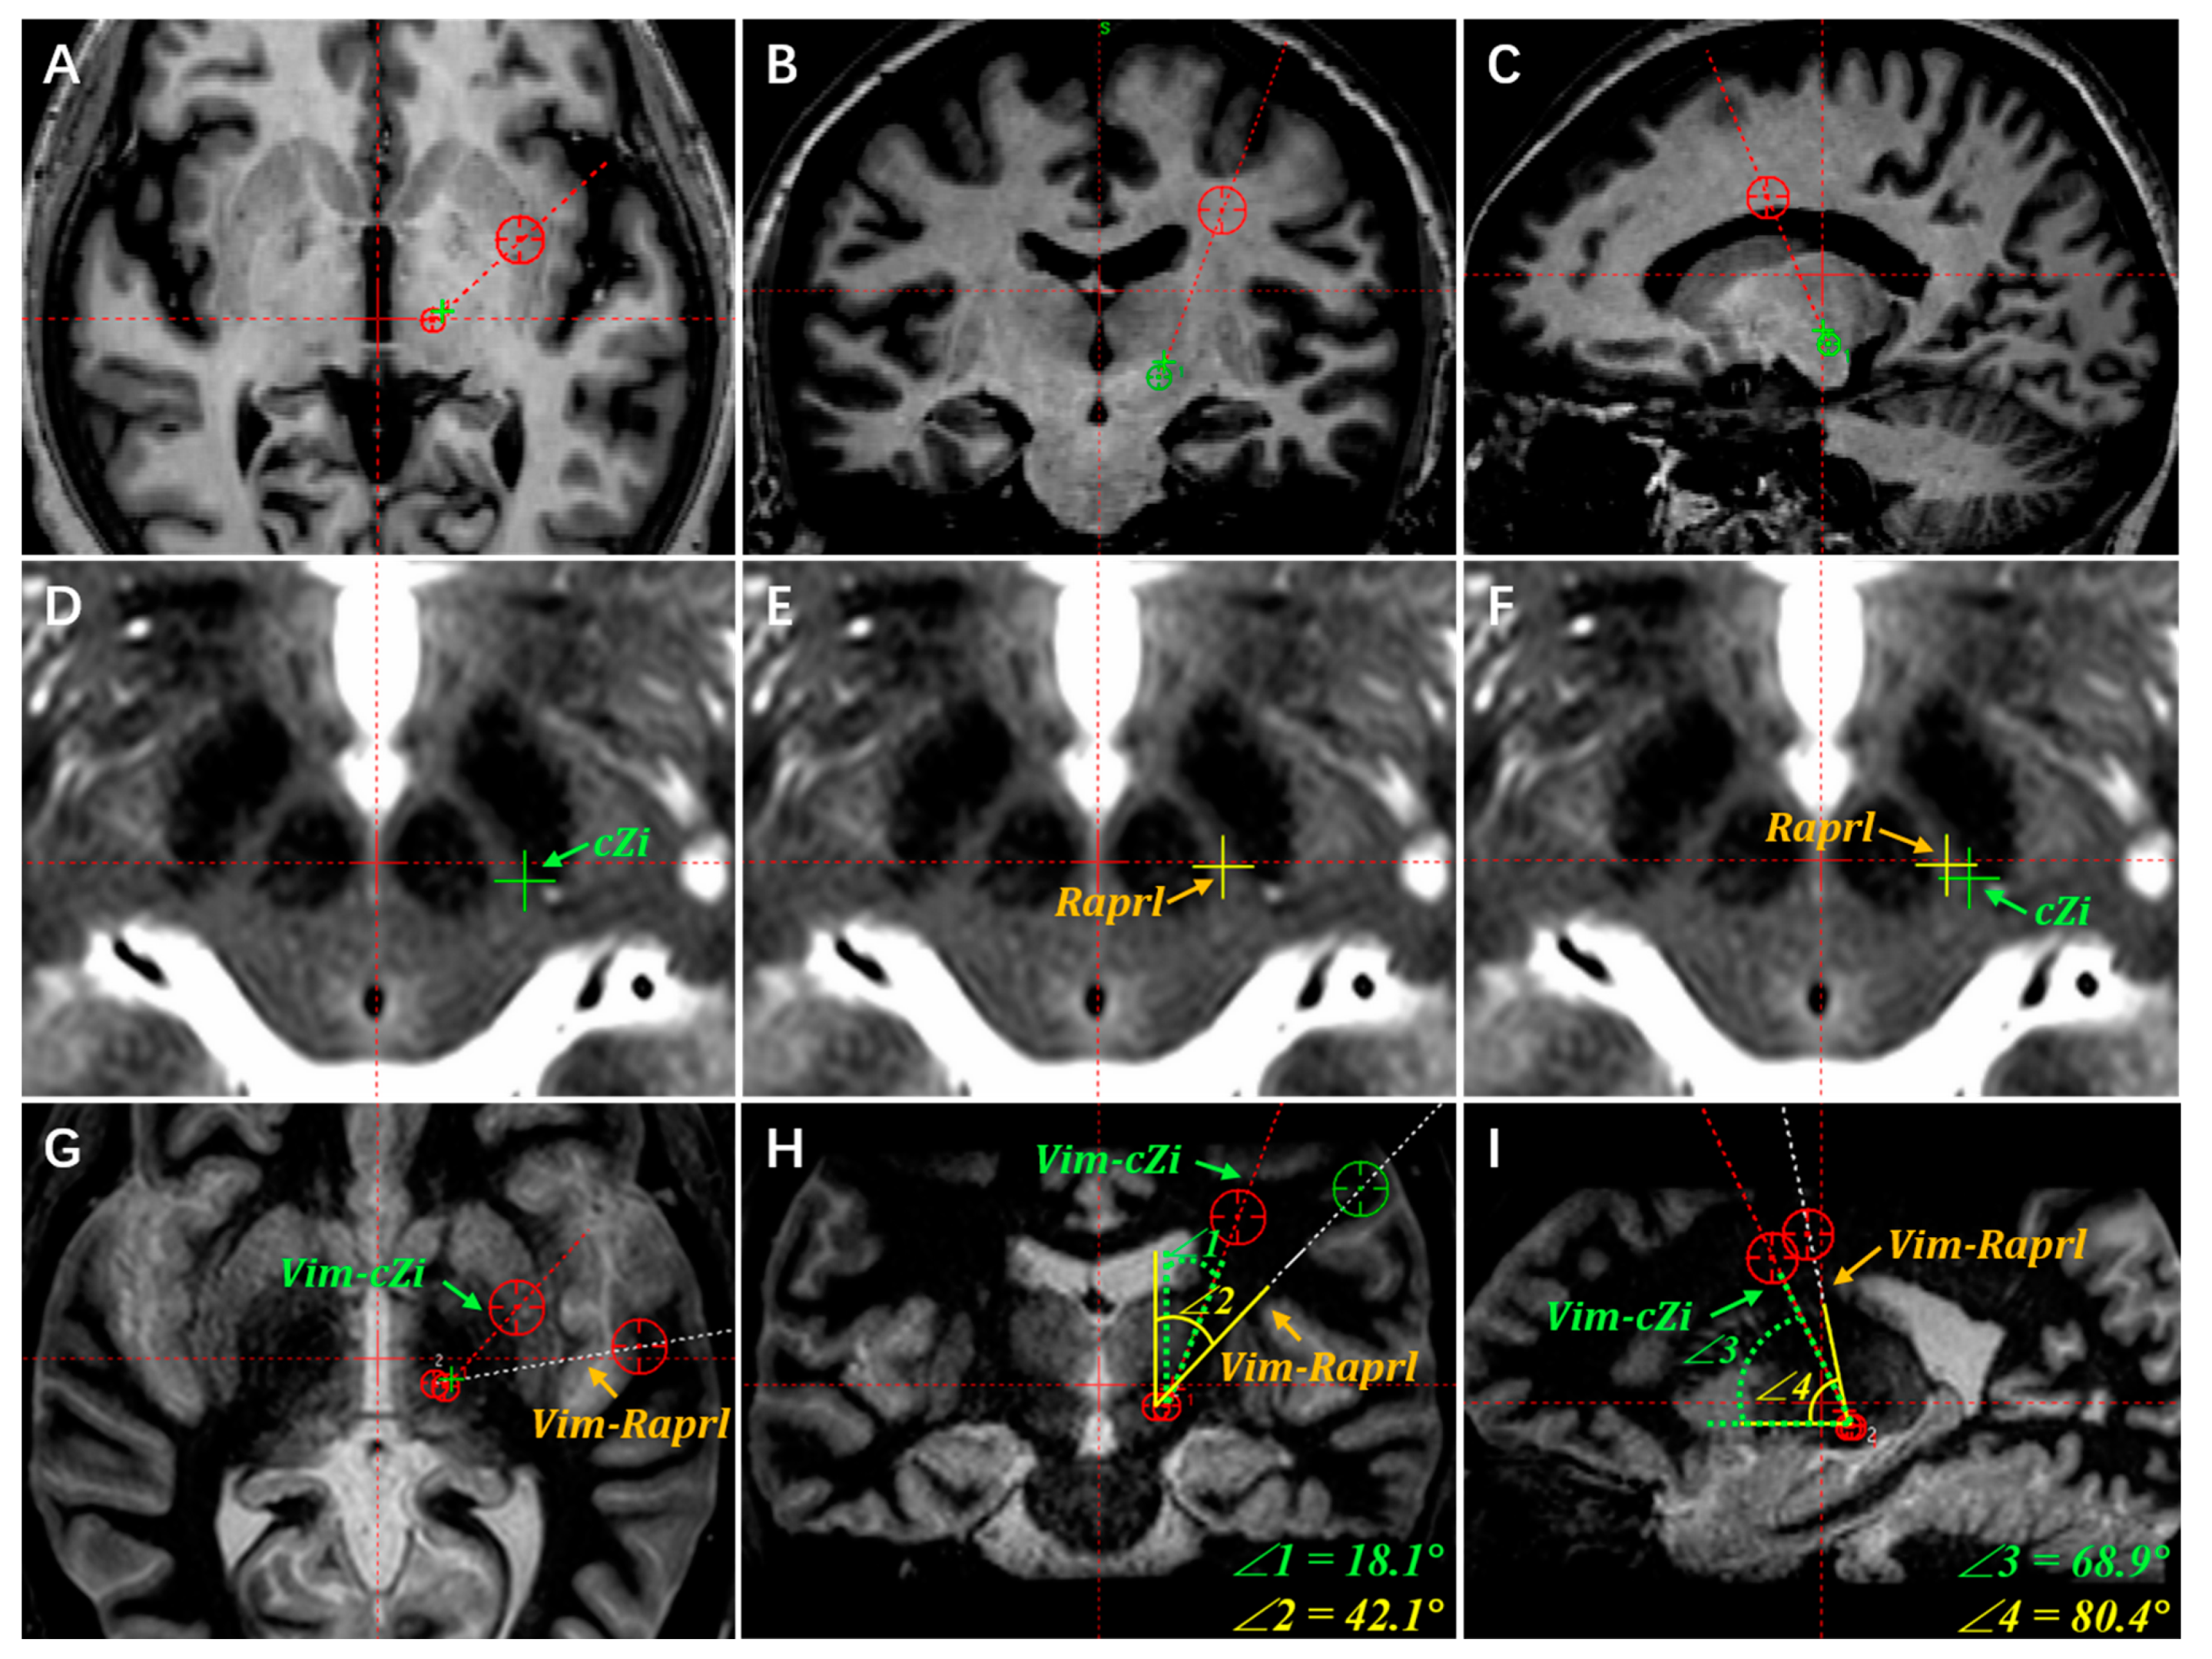

3.1. Locating the Vim and PSA Targets

3.2. Targets Adjustment